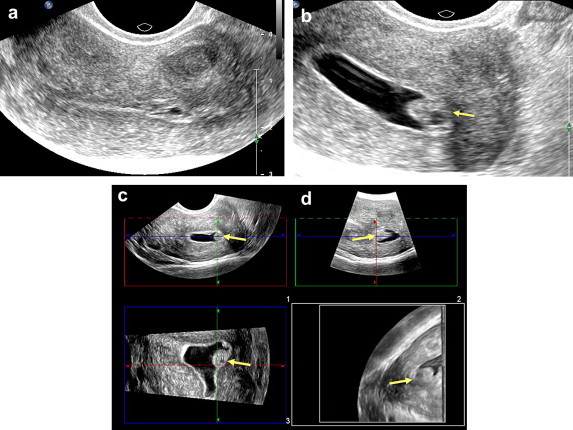

Fig. 1.

Septate uterus with a polyp in one hemicavity. (a) Transvaginal ultrasound: sagittal scan of the uterine body. (b) 2-D sonohysterography: the intracavitary polyp is clearly visualized (arrow). (c) 3-D sonohysterography: multiplane reconstruction. Visualization in the coronal plane allows precise assessment of the septum (S) and polyp (arrow) in one of the hemicavities.

Fig. 2.

Sessile polyp arising from the left wall. (a) Transvaginal ultrasonography provides inadequate visualization of the lesion. (b) 2-D sonohysterography provides good visualization of the intracavitary polyp (arrow). (c) 3-D sonohysterography with multiplane reconstruction and (d) 3-D sonohysterography with volumetric reconstruction: coronal scan of the cavity provides precise information on the polyp's attachment to the juxta-tubal endometrium (arrow).

Fig. 3.

Congenital malformation. (a) 2-D sonohysterography: The axial section suggests the presence of a fundus defect (arrow). (b) 3-D sonohysterography with multiplane reconstruction reveals an arcuate (or saddle-shaped) uterus (arrow).

Fig. 4.

Assessment of the uterine fundus. (a) 2-D sonohysterography: Axial scan of the uterus reveals evidence suggestive of a small lesion in the fundus (arrow). (b) 2-D sonohysterography: the fundus lesion is clearly visualized (arrow). The irregular appearance of the wall is caused by peristalsis.

Fig. 5.

Value of coronal-plane scans. (a) A polyp located in the tubal angle can be fully explored on the coronal scan (arrow). (b) A submucosal myoma (associated with menometrorrhagia) can be seen protruding into the cavity of uterus. The fundus malformation can be seen better on the coronal reconstruction (arrow).